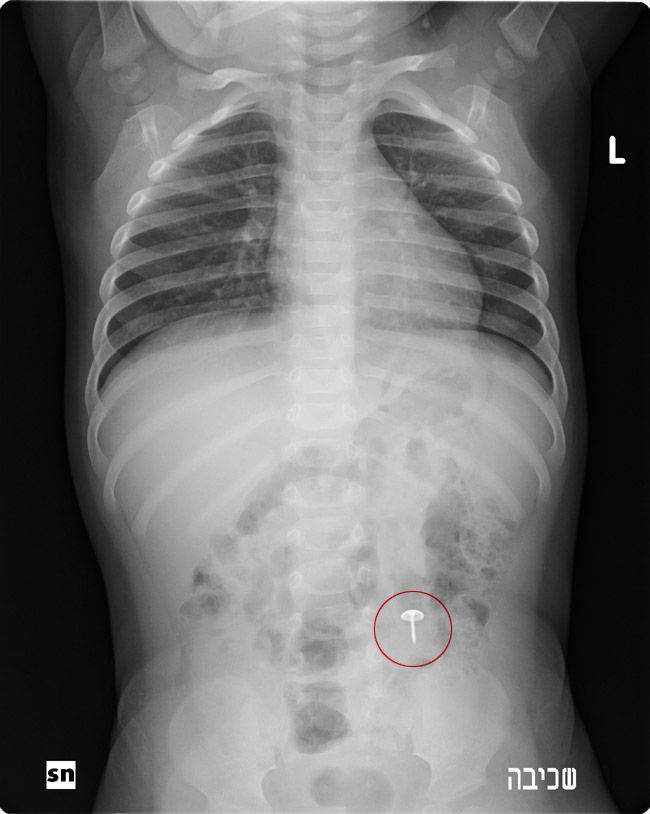

החובשים שהגיעו לבית לא הצליחו להוציא את המסמר שבלעה התינוקת, ופינו את הילדה להמשך טיפול בבית החולים הדסה עין כרם, שם התברר באמצעות צילום רנטגן כי המסמר נמצא עדיין בתוך גופה של התינוקת ונקבע לה מועד לניתוח על מנת להוציאו.

לדבריו, "בבוקר, כמה שעות לפני הניתוח, שוב נערך לילדה צילום רנטגן אלא שהצילום גילה כי המסמר איננו, לפני שהבנו מה קרה, התברר כי המסמר יצא זמן מה קודם לכן בצורה טבעית מבלי לגרום לגוף כל נזק".